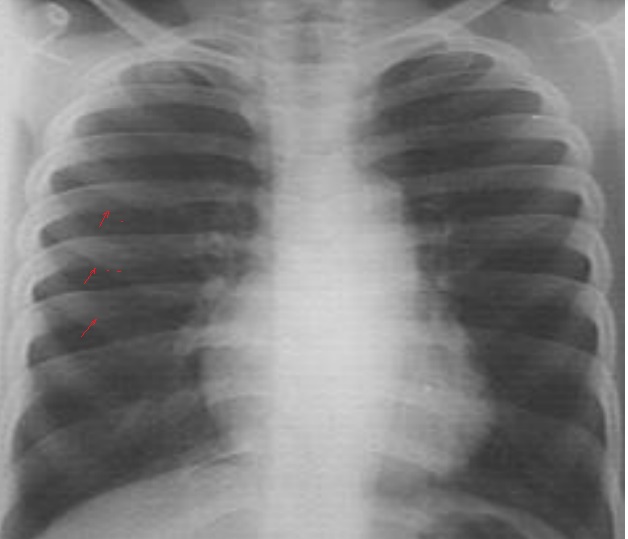

Image radiologique de cliche1

de face AP d'une syndrome de Poland avec aplasia dui

muscle pectoralis droit . Aspect de hyperluscence du

poumon droit est très net |

Cliche de face PA d'une

syndrome de Poland avec de hypolasia du muscle

pectoralis majeur droit . Ce qui donne une aspect

radiologique est hyperluscence du 1/2 superieure du

champ pulmonaire droit |